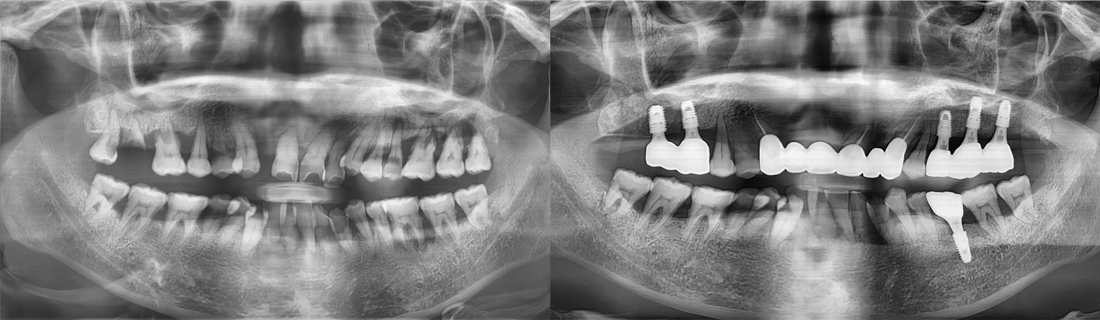

백년치과를 만나기 전과 후

나의 치아 사례와 비슷한 환자분들이 치료 후 어떻게 변화되었는지 직접 확인해보세요.

백년치과 임플란트를 만나기 전과 후